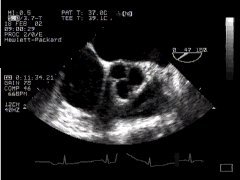

The principles of multiplane imaging are the same as for biplane imaging - the probe is simply a lot more convenient to use. Multiplane imaging has now become the standard. You will find that it's often difficult to cut anatomical structures such as the aortic valve at right angles with biplane imaging. Compare the following two images:

CLICK FOR VIDEO: aortic valve (basal)